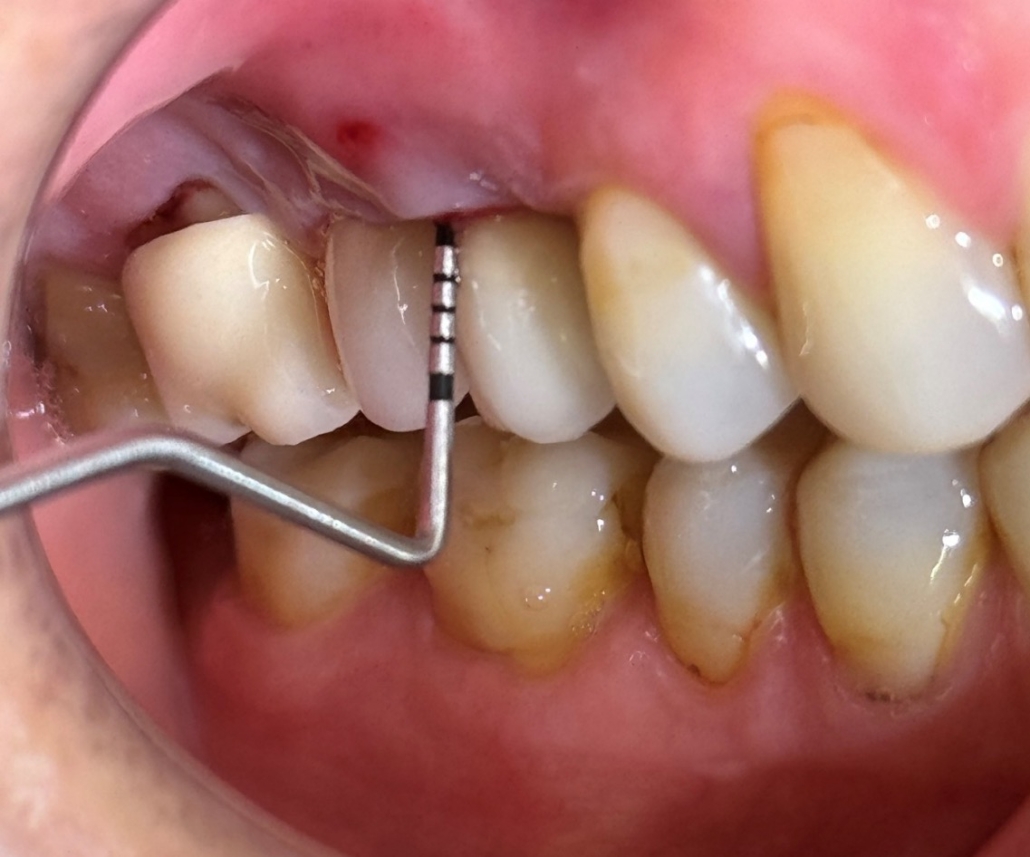

Periimplantitis je upalno patološko stanje koje zahvaća tkiva u neposrednoj okolini dentalnog implantata, pri čemu dolazi do upale periimplantatne sluznice i postupnog gubitka koštanog potpornog tkiva. Kliničke manifestacije periimplantitisa uključuju upalu, krvarenje pri sondiranju, supuraciju, povećanu dubinu sondiranja i gubitak kosti (Slika 1.). Upala mekih tkiva obično se otkriva krvarenjem pri sondiranju, dok se gubitak kosti prepoznaje na radiografskim snimkama kao ˝krater˝ oko implantata uz povećane dubine sondiranja (Slika 2.). Dubina sondiranja može ukazivati na ozbiljnost bolesti i korelira s gubitkom kosti, čija brzina varira među pacijentima (1). Periimplantitis se često razvija kod pacijenata s prethodnom anamnezom uznapredovalog parodontitisa, lošom kontrolom plaka te nedostatkom redovite terapije održavanja nakon implantološkog zahvata.